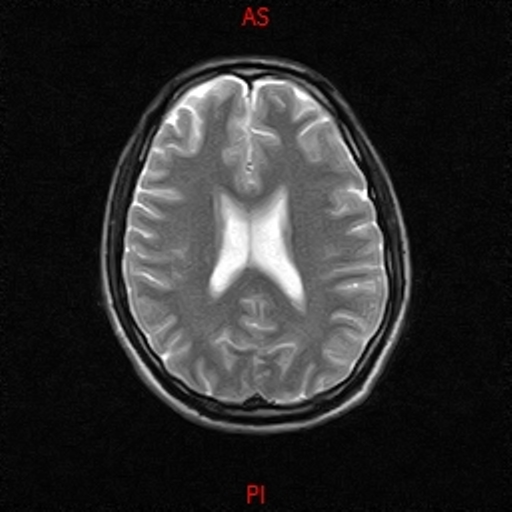

• RESONANCIA NORMAL CRANEAL T2 AXIAL